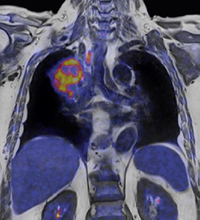

■参考:「Biograph mMR」で撮影された画像

1. 完全な全身同時撮影が行えるため,病変の広がりを詳細に評価することが可能

3. MR画像から得られる解剖学的情報だけでなく,同時に得られるPET画像から病変組織の詳細な代謝情報を把握することが可能

既に研究発表において,本システムを用いたがん診断において高い有用性が海外において多数報告されている。CT画像では評価の難しい領域におけるMR画像の有効性とPET画像のがん細胞の活動評価をあわせることで,従来診断の難しい領域においても正確な評価が行える。例えば,骨盤部の検査において,撮影のタイミングが異なると,排尿の影響により膀胱の大きさが変化するために周囲の位置情報が変化するが,「Biograph mMR」では,MRIとPETの撮影の時間差がないために,空間的にも完全に一致した形態情報が得られ,リンパ節等の微小病変の位置関係まで正確に一致した情報が得られる。